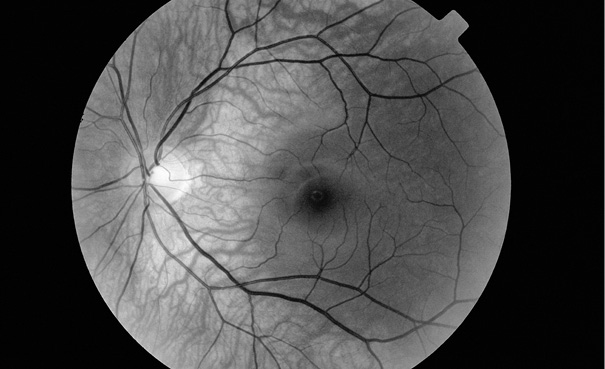

Активная переоценка окружения и есть причина, почему в 1980-е годы многие люди замечали, что текст в книгах отливает красноватым оттенком. Напомню, что в тот период началось массовое использование компьютерных мониторов для набора и редактирования текстов. Но у тех ранних экранов, в отличие от современных, возможности цветопередачи были ограничены только зеленым цветом на черном фоне. В итоге множеству людей приходилось по многу часов сосредоточенно смотреть на набранные зеленым шрифтом горизонтальные строки. И потому, когда они потом открывали бумажную книгу, строки черного шрифта оттенялись в их восприятии дополнительным цветом — красноватым. Мозг приспосабливался к реальности, где горизонтальные строки имели зеленый цвет, соответствующим образом менялась и их внутренняя реальность. Пользователи компьютеров испытывали ту же оптическую иллюзию, глядя на логотип IBM, украшавший обложку фирменных дискет компании (рис. 7.2): в их глазах он приобретал красноватый оттенок. Дизайнеры IBM пребывали в большом замешательстве: кто-кто, а они наверняка знали, что черно-белые обложки печатаются в типографии без добавки красной краски. Но клиенты, хоть убейся, доказывали, что логотип имеет красноватый оттенок. ![]() Рис. 7.2. Логотип IBM IBM Вывод таков: ни движение в реальном мире, ни то, насколько тверда земля под ногами, ни проплывающие мимо картины, когда мы переставляем ноги, ни насыщенность линий каким-либо конкретным цветом — ничто из перечисленного не предопределено в нашем мозге генетикой, а настраивается под влиянием нашего чувственного опыта. Как ожидаемое становится невидимым Если смотреть на однообразную (в смысле отсутствия каких-либо особенностей) одноцветную картину (предположим, желтую), мозг быстро отметит этот цвет как нейтральный. Сделайте вот что: возьмите желтый шарик для пинг-понга и аккуратно разрежьте на две половинки. Поместите по одной на каждый глаз, и мир тут же предстанет перед вами сплошным желтым одеялом. Однако очень скоро вы вообще перестанете воспринимать окружающее и перед глазами появится сплошная бесцветная пелена, словно вы лишились зрения. Зрительная система пришла к заключению, что мир пожелтел и теперь это нормально, а потому исключила желтый цвет из вашего восприятия, чтобы усилить чувствительность к другим переменам в реальности. Для подобного «исчезновения» цвета необязательно, чтобы картина была лишена каких-либо характерных особенностей. В 1804 году швейцарский врач Игнац Трокслер заметил странную вещь: если зафиксировать взгляд в центральной точке посреди расположенных по окружности кружков, происходящая на периферии зрения кипучая активность в конце концов исчезнет. На рис. 7.3 фиксируйте взгляд на черной точке посреди картинки с расположенными по периферии кружочками в течение примерно десяти секунд. Не переводя взгляд на кружочки, вы заметите, что они исчезают, словно растворяясь в воздухе, и вскоре осознаете, что смотрите в пустое серое пространство. ![]() Рис. 7.3. Эффект Трокслера. Удерживайте взгляд на центральной точке, и темные кружочки постепенно исчезнут, как будто их и не было Эта иллюзия, известная как эффект Трокслера, демонстрирует, что неизменный стимул, наблюдаемый боковым зрением, скоро исчезнет. Почему так происходит? Потому что полезная информация должна обновляться, а все, что сохраняет неизменность, система попросту игнорирует. Тогда почему ваша кухня или кабинет со всеми неподвижными предметами обстановки по-трокслеровски не исчезают из вашего зрительного восприятия? Во-первых, большинство объектов мира состоит из острых краев и углов, а за них зрительной системе зацепиться проще, чем за круги с монотонными очертаниями. Однако на то имеется и более основательная причина. Хотя вы в целом этого не осознаёте, ваши глаза постоянно скачут и прыгают по сторонам. Вглядитесь в глаза своей подруги: вы заметите, что ее глазные яблоки совершают по три быстрых скачка в каждую секунду бодрствования. Если наблюдать еще внимательнее, обнаружится, что в промежутках между скачками глазные яблоки постоянно слегка подрагивают5. Может быть, с ней что-то не в порядке? Ничуть. Эти быстрые движения — как крупные, так и мелкие — поддерживают свежесть изображения на сетчатке. Хотя ваша визави этого не осознаёт, ее глаза усердно трудятся, чтобы поддерживать постоянно меняющийся образ реальности. Зачем им эта морока? Дело в том, что любой образ, прочно зафиксированный на сетчатке в одном и том же положении, через какое-то время станет невидимым. Вот как можно доказать себе правоту этого утверждения. Если вы носите контактные линзы, возьмите маркер и нарисуйте на внешней стороне одной из них, прямо посередине, крошечный значок. Вернув линзу в глаз, вы заметите, что на ней что-то изображено, однако это продлится недолго: крохотный рисунок быстро растворится в невидимости6. Данный феномен подчеркивает основополагающий факт: мозг чутко отслеживает перемены. Как при эффекте Трокслера, неизменные особенности обстановки дают мало информации об окружающей реальности. Вся значимая информация поступает от элементов обстановки, пребывающих в состоянии изменения. Если вы не носите контактные линзы, не расстраивайтесь: вы и так, сами того не подозревая, иногда проводите подобный эксперимент. В задней части глаза, над сетчаткой, пролегает сеть кровеносных сосудов. Она должна накладываться на все, что вы видите, поскольку располагается между фоторецепторами и видимым миром. Однако в вашем восприятии эта сеть невидима: она зафиксирована относительно сетчатки так же, как рисунок на контактной линзе. Сколько бы движений ни делали ваши глаза, они никогда не «обновляют» образ сосудов, которые находятся между вами и миром, но в какой-то момент исчезают, как по мановению волшебной палочки (рис. 7.4). ![]() Рис. 7.4. Сетчатка покрыта густой сеткой кровеносных сосудов. А поскольку они располагаются перед фоторецепторами, то есть накладываются на видимую нам картину мира, мы, по идее, должны видеть их во множестве. Однако постоянное и неизменное расположение сосудов не дает нам новой информации, поэтому зрительная система полностью игнорирует их Paul Parker / Science Photo Library Вы могли на какие-то мгновения заметить их при осмотре у офтальмолога, когда доктор светил вам в глаза точечным фонариком7. Под лучом направленного света сосуды могут отбрасывать тени под необычным углом, и тогда зрительная система внезапно улавливает их. Так происходит потому, что в вашей сетчатке только что случилось нечто непредвиденное, и это единственный случай, когда вы можете увидеть густую сеть сосудов, заслоняющую обзор. (Если вы никогда не видели сосудистую систему собственного глаза, отложите книгу, пойдите в темную комнату и посветите себе в глаз точечным фонариком, но обязательно под углом. Вы увидите, как перед глазами появляются переплетения сосудов. Зрительная система довольно быстро приспособится к внезапно вспыхивающему свету, и хитрость заключается в том, чтобы менять угол освещения, желая сохранить изображение.) |